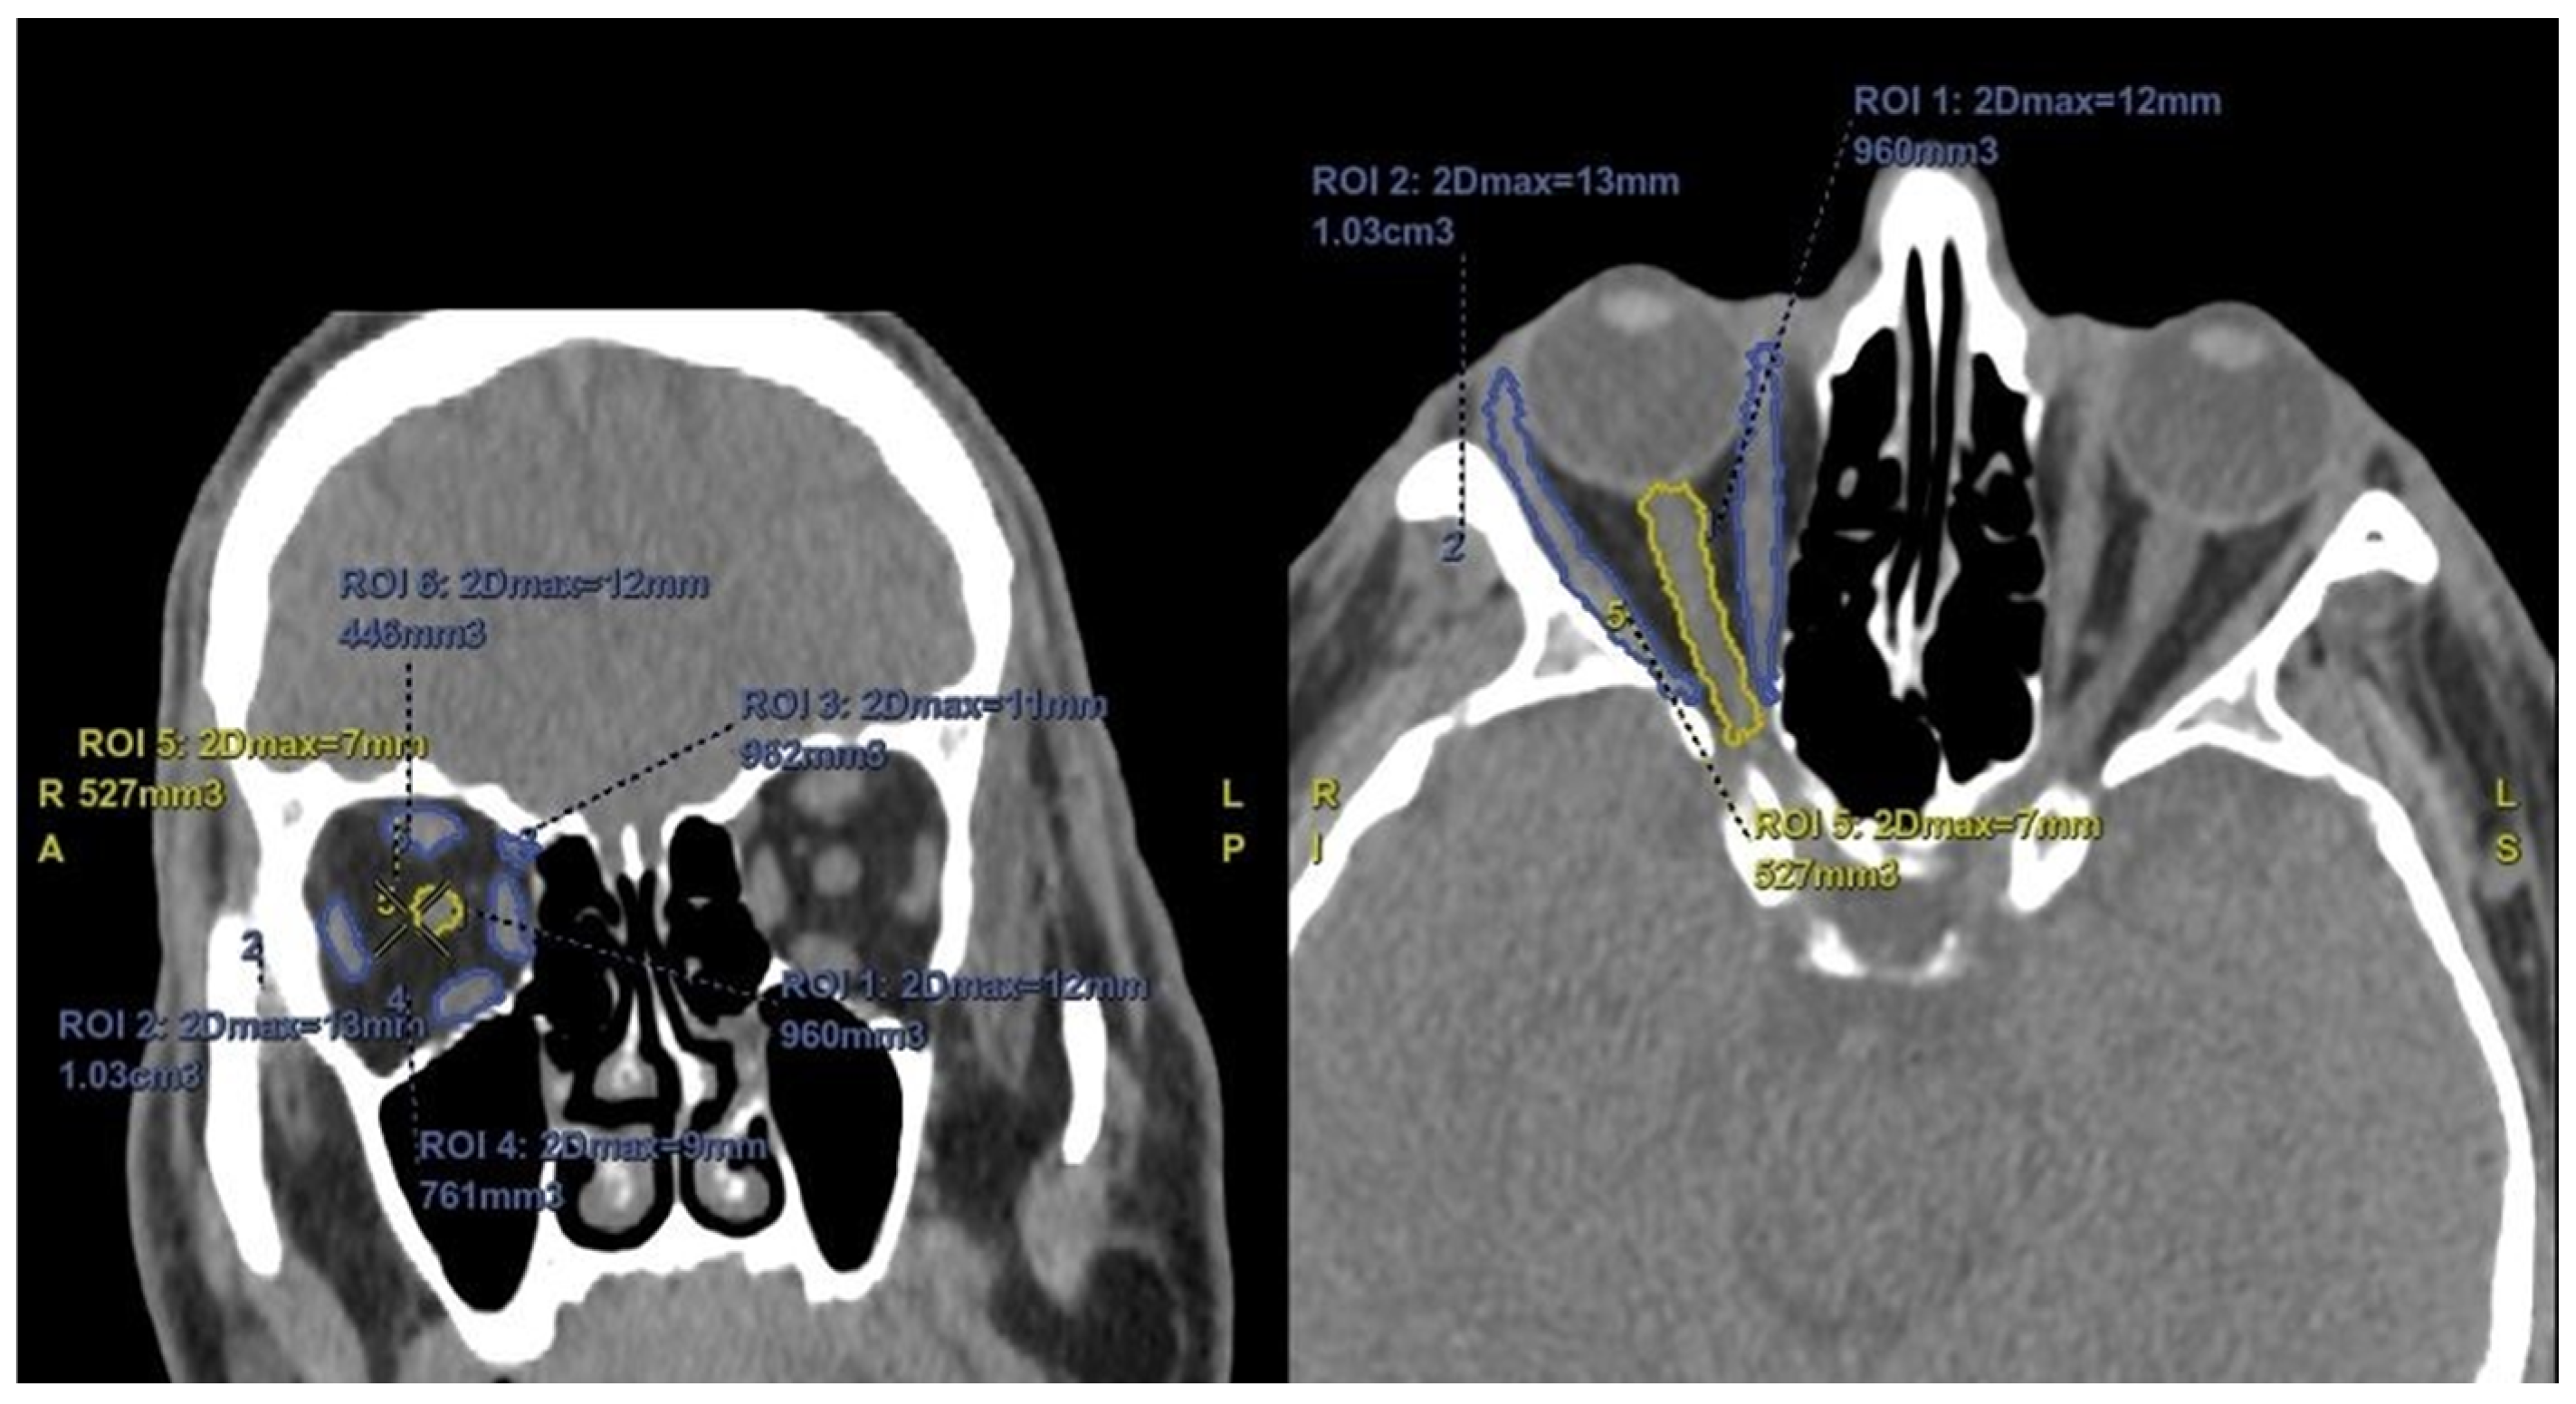

The average enophthalmos measurements and tissue volumes obtained from the CT images are shown in Table 2. Accordingly, the mean enophthalmos values on the side treated with PGA were found to be slightly lower compared to the untreated side; however, this difference did not reach statistical significance (15.5 ± 2.0 mm vs. 16.1 ± 1.4 mm, respectively) (p = 0.07). In 29 patients (72.5%), the enophthalmos measurements on the treated side were smaller compared to the untreated side, with a difference of 2 mm or more in 7 patients (17.5%) (Figure 2).

Figure 2. Enophthalmos measurements of a patient using a latanoprost–timolol fixed combination in the left eye for 24 months show a difference of more than 2 mm between the two eyes.